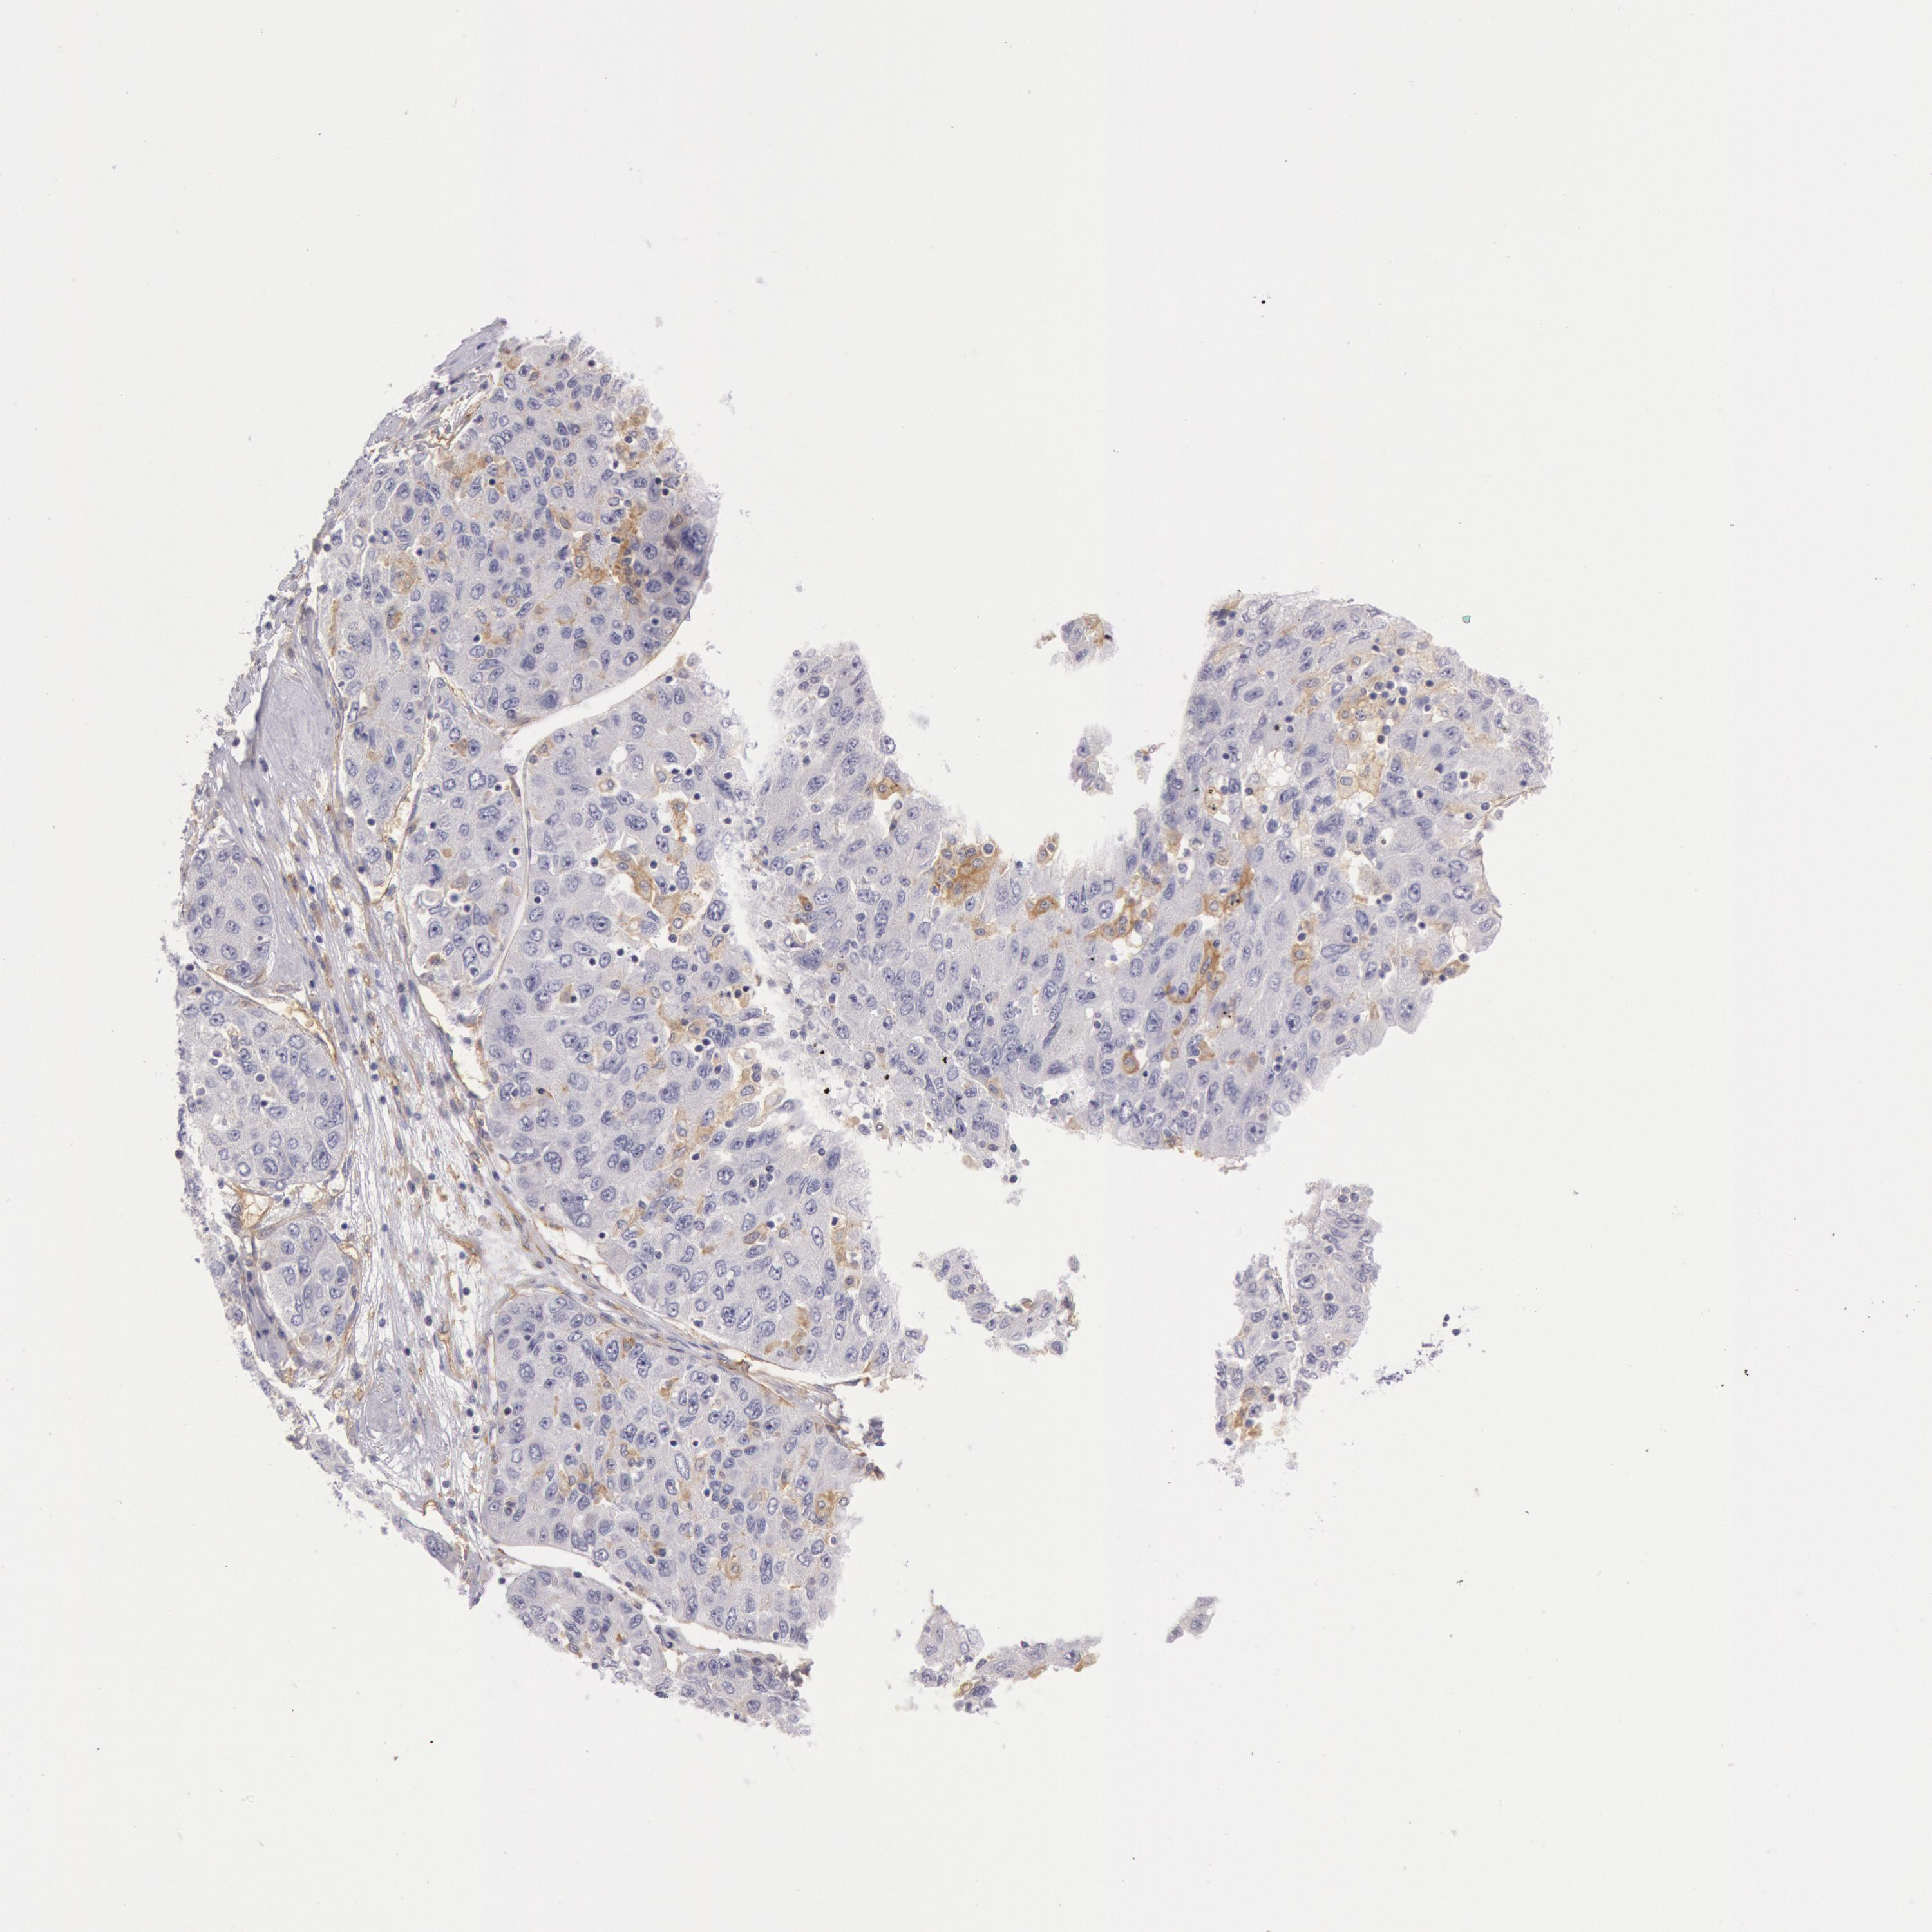

LIVER CANCER - Protein expressioni

A mouse-over function shows sample information and annotation data. Click on an image to view it in a full screen mode. Samples can be filtered based on level of antibody staining by selecting one or several of the following categories: high, medium, low and not detected. The assay and annotation is described here.

Note that samples used for immunohistochemistry by the Human Protein Atlas do not correspond to samples in the TCGA dataset.

Antibody stainingi

Antibody staining in the annotated cell types in the current human tissue is reported as not detected, low, medium, or high, based on conventional immunohistochemistry profiling in selected tissues. This score is based on the combination of the staining intensity and fraction of stained cells.

Each image is clickable and will lead to virtual microscopy that enables deeper exploration of all samples and also displays staining intensity scores, fraction scores and subcellular localization as well as patient and tissue information for each sample.

Antibody HPA001356

Staining

High

Medium

Low

Not detected

Intensity

Strong

Moderate

Weak

Negative

Quantity

>75%

75%-25%

<25%

None

Location

Nuclear

Cytoplasmic/membranous

Cytoplasmic/membranous,nuclear

Carcinoma, Hepatocellular, NOS

Cholangiocarcinoma